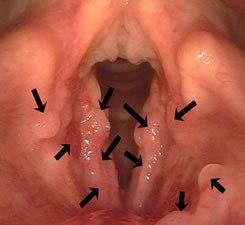

پاپیلوماها تومورهای زگیلی هستند که منشا ویروسی دارند و در حفره های مرطوب و تاریک مجرای تنفسی و غالبا در حنجره ی کودکان کم سن و سال به وجود می آیند. این توده با بزرگتر شدن باعث گرفتگی صدای شدید و خطری برای مسیر تنفسی به حساب می آید زیرا به دلیل حجم زیاد مانع از تبادل هوا با ریه ها می گردد.

به همین دلیل بررسی گرفتگی صدای کودکان در ١٠ روز اول بسیار حیاتی است. از آنجا که این توده پس از جراحی به احتمال زیاد برگشت پذیر است فقط در مواقعی که خطر جدی برای تنفس ایجاد کند جراحی می شود. اکثر پاپیلوماها پس از سن بلوغ متوقف می شوند.